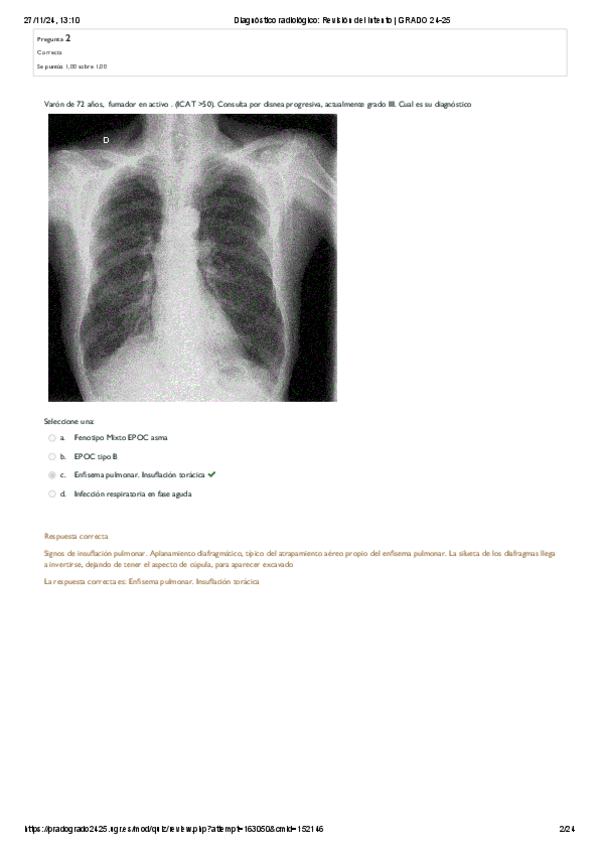

He publicado nuevos practicas de 3º Bases de la Medicina Interna II: evaluacion-ecografia.pdf

PRACTICA-ECOGRAFIA.pdf